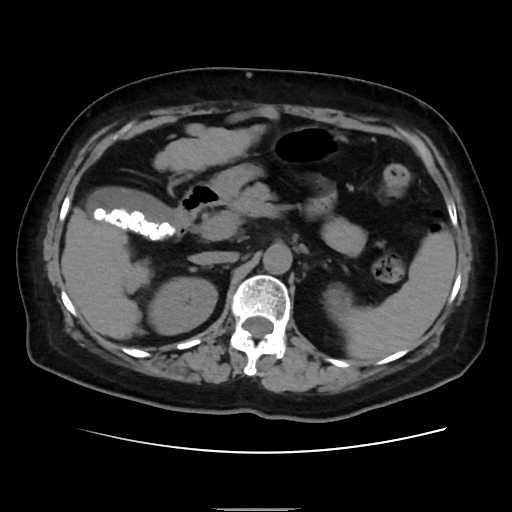

腹部

尿管結石

胆石